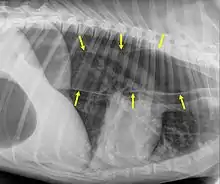

Megaesophagus

Megaesophagus, also known as esophageal dilatation, is a disorder of the esophagus in humans and other mammals, whereby the esophagus becomes abnormally enlarged. Megaesophagus may be caused by any disease which causes the muscles of the esophagus to fail to properly propel food and liquid from the mouth into the stomach (that is, a failure of peristalsis). Food can become lodged in the flaccid esophagus, where it may decay, be regurgitated, or maybe inhaled into the lungs (leading to aspiration pneumonia).[1]